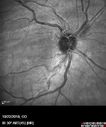

Familial Exudative Vitreoretinopathy - FEVR - Stage 4b OD384 views10 year old child with poor vision OD from birth. The left eye had vascular remodelling in the temporal periphery with preretinal abnormalitlies seen on OCT. The patient never returned for a fluorescein angiogram. Left eye is either stage 1 or stage 2. no family historyJan 01, 2019

Familial Exudative Vitreoretinopathy - FEVR - Stage 4b OD582 views10 year old child with poor vision OD from birth. The left eye had vascular remodelling in the temporal periphery with preretinal abnormalitlies seen on OCT. The patient never returned for a fluorescein angiogram. Left eye is either stage 1 or stage 2. no family historyJan 01, 2019